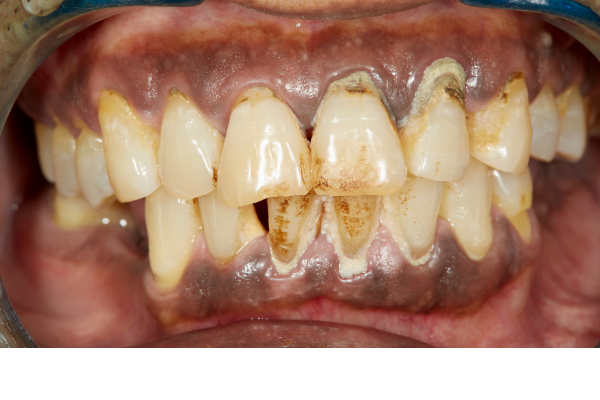

Advanced stage periodontal disease.

Surgery is often required when the gums have started to recede from the crowns of the teeth, when gum tissue lifts away from the teeth causing pockets, and/or when bone loss occurs as a result of severe infection.